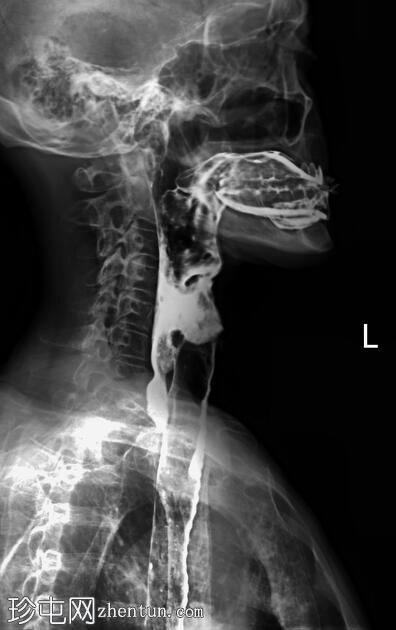

侧位

正位和侧位图像显示造影剂在咽部积聚,并伴有钡剂误吸至气道和支气管树。未见

肺

实变。

此外,胸椎存在退行性改变,表现为终板硬化和边缘骨赘形成。

透视图像显示钡剂误吸覆盖喉部和气管支气管树。